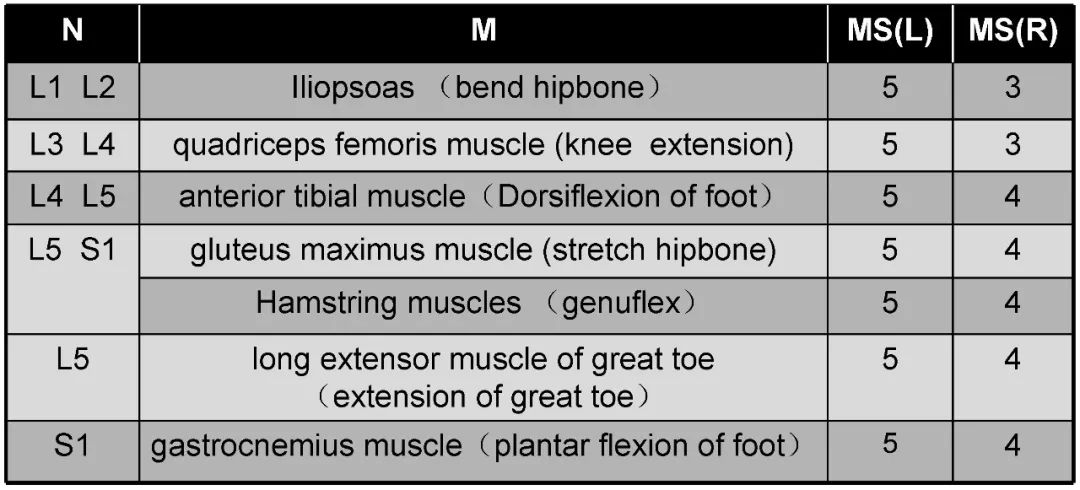

病史:M, 34 y/o

Present History:

Numbness of right lower limb for 2 months, weakness for 1 week

Urination disorder

Past History(-):

Body Weight: 120Kg; BMI: 39.5

术后3个月: